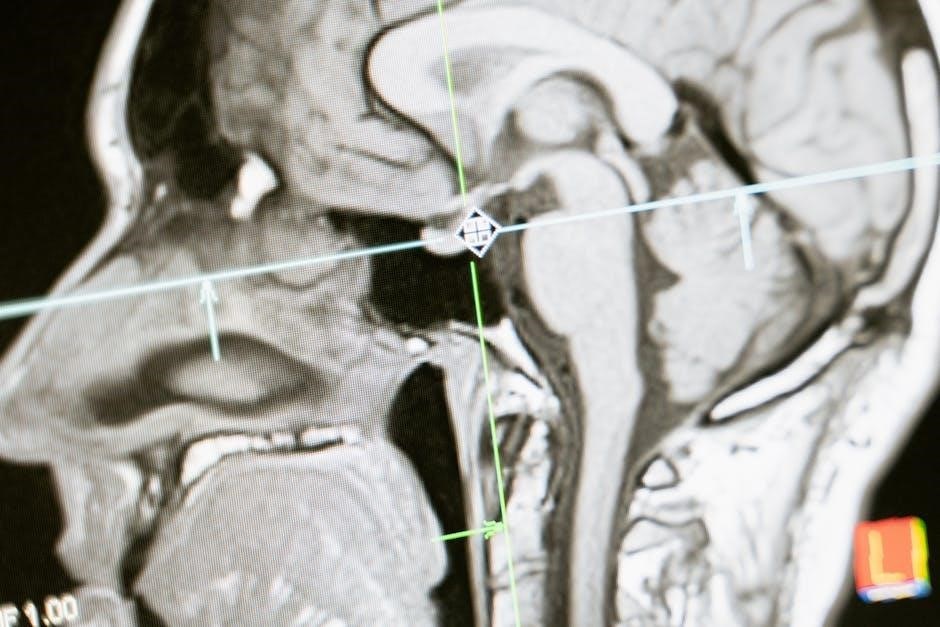

Anatomy is the scientific study of the structure of organisms‚ focusing on the internal and external organization of living beings. Derived from the Greek word anatomē (dissection)‚ it examines the physical arrangement of tissues‚ organs‚ and systems. The scope of anatomy encompasses both macroscopic and microscopic structures‚ providing a foundational understanding of how organisms function. In the context of the head and neck‚ anatomy includes the study of bones‚ muscles‚ nerves‚ glands‚ and blood vessels‚ essential for medical professionals. Textbooks like Textbook of Head and Neck Anatomy and resources such as Clinical Head and Neck Anatomy for Surgeons detail these structures‚ emphasizing their clinical relevance and surgical significance.

The study of head and neck anatomy is crucial for understanding the complex interrelationships of structures in this region. It is essential for medical professionals‚ particularly surgeons‚ dentists‚ and radiologists‚ due to the high concentration of nerves‚ blood vessels‚ and glands. Mastery of this anatomy aids in diagnosing and treating conditions like tumors‚ infections‚ and trauma. It also underpins surgical planning‚ ensuring precise dissection and minimizing complications. For educators and students‚ it provides a foundational framework for learning and teaching. Resources like Anatomy of the Head and Neck emphasize its clinical relevance‚ making it indispensable for both academic and practical applications in healthcare.